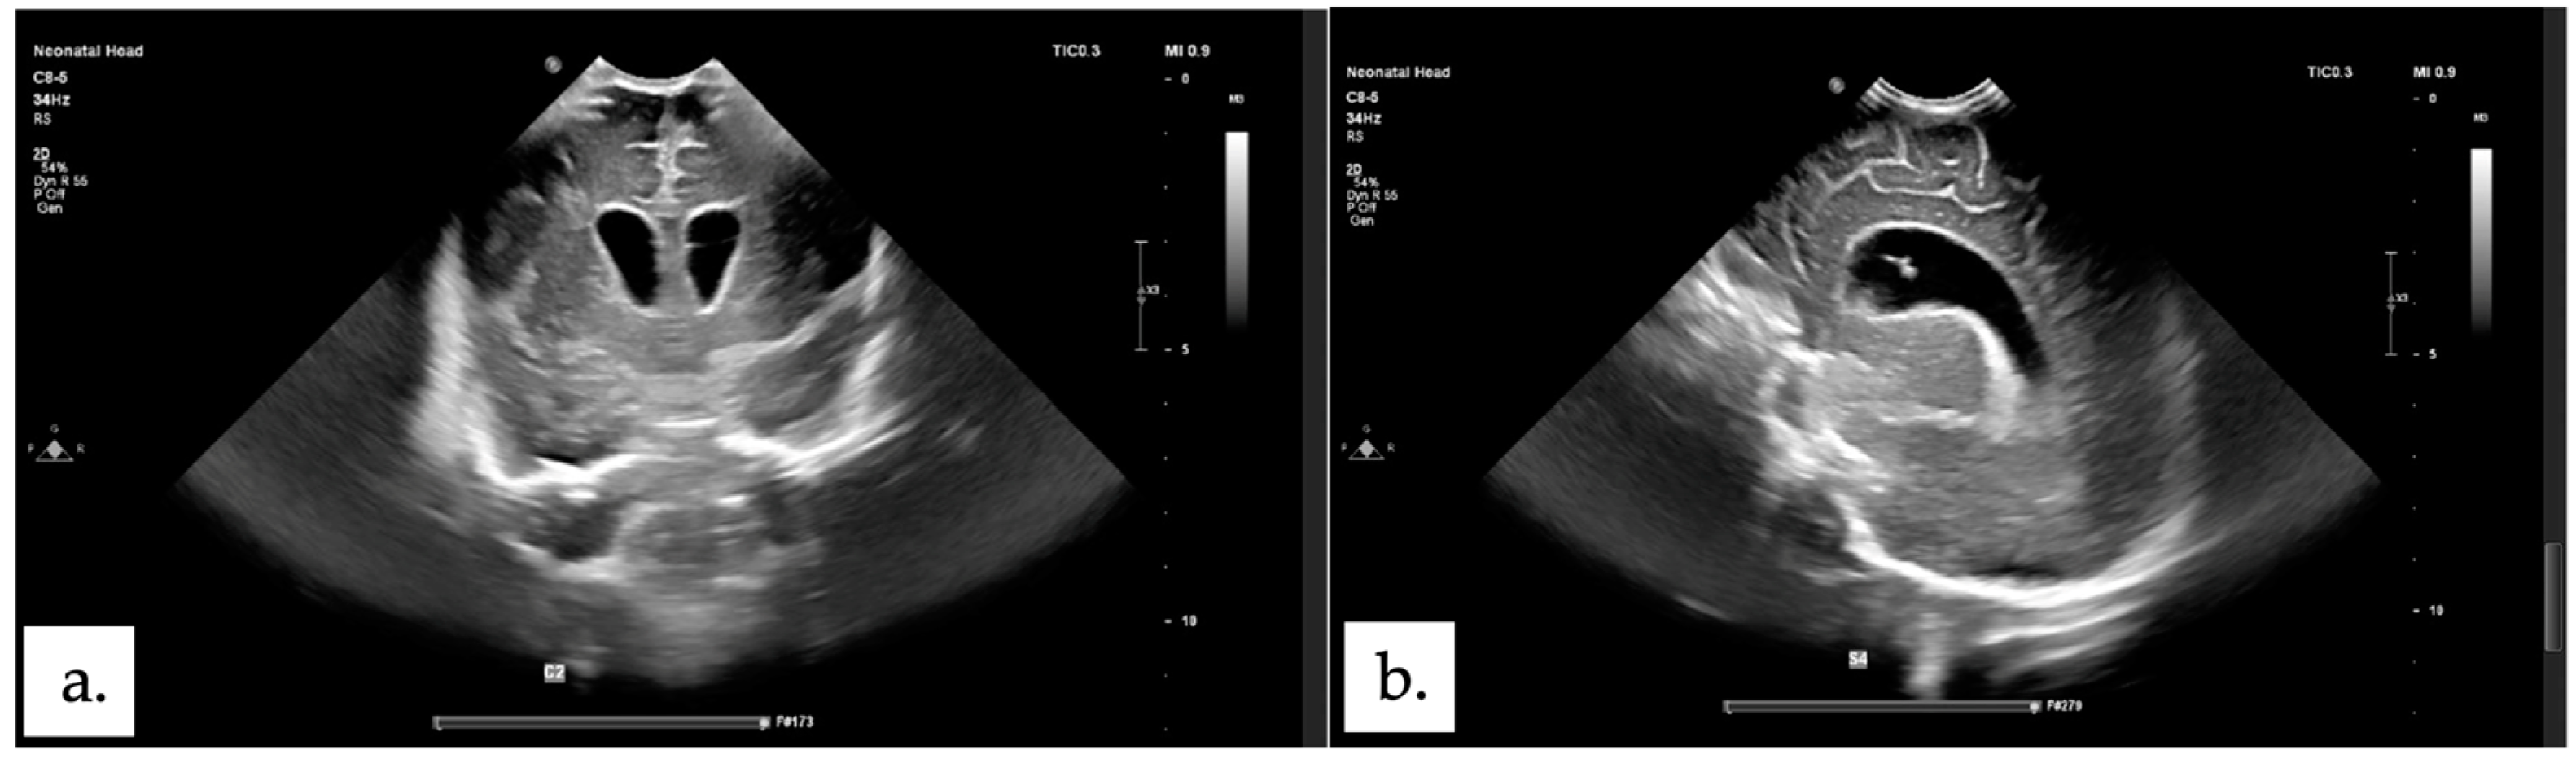

2.1. Patient 1

2.2. Patient 2

2.3. Patient 3

2.4. Patient 4